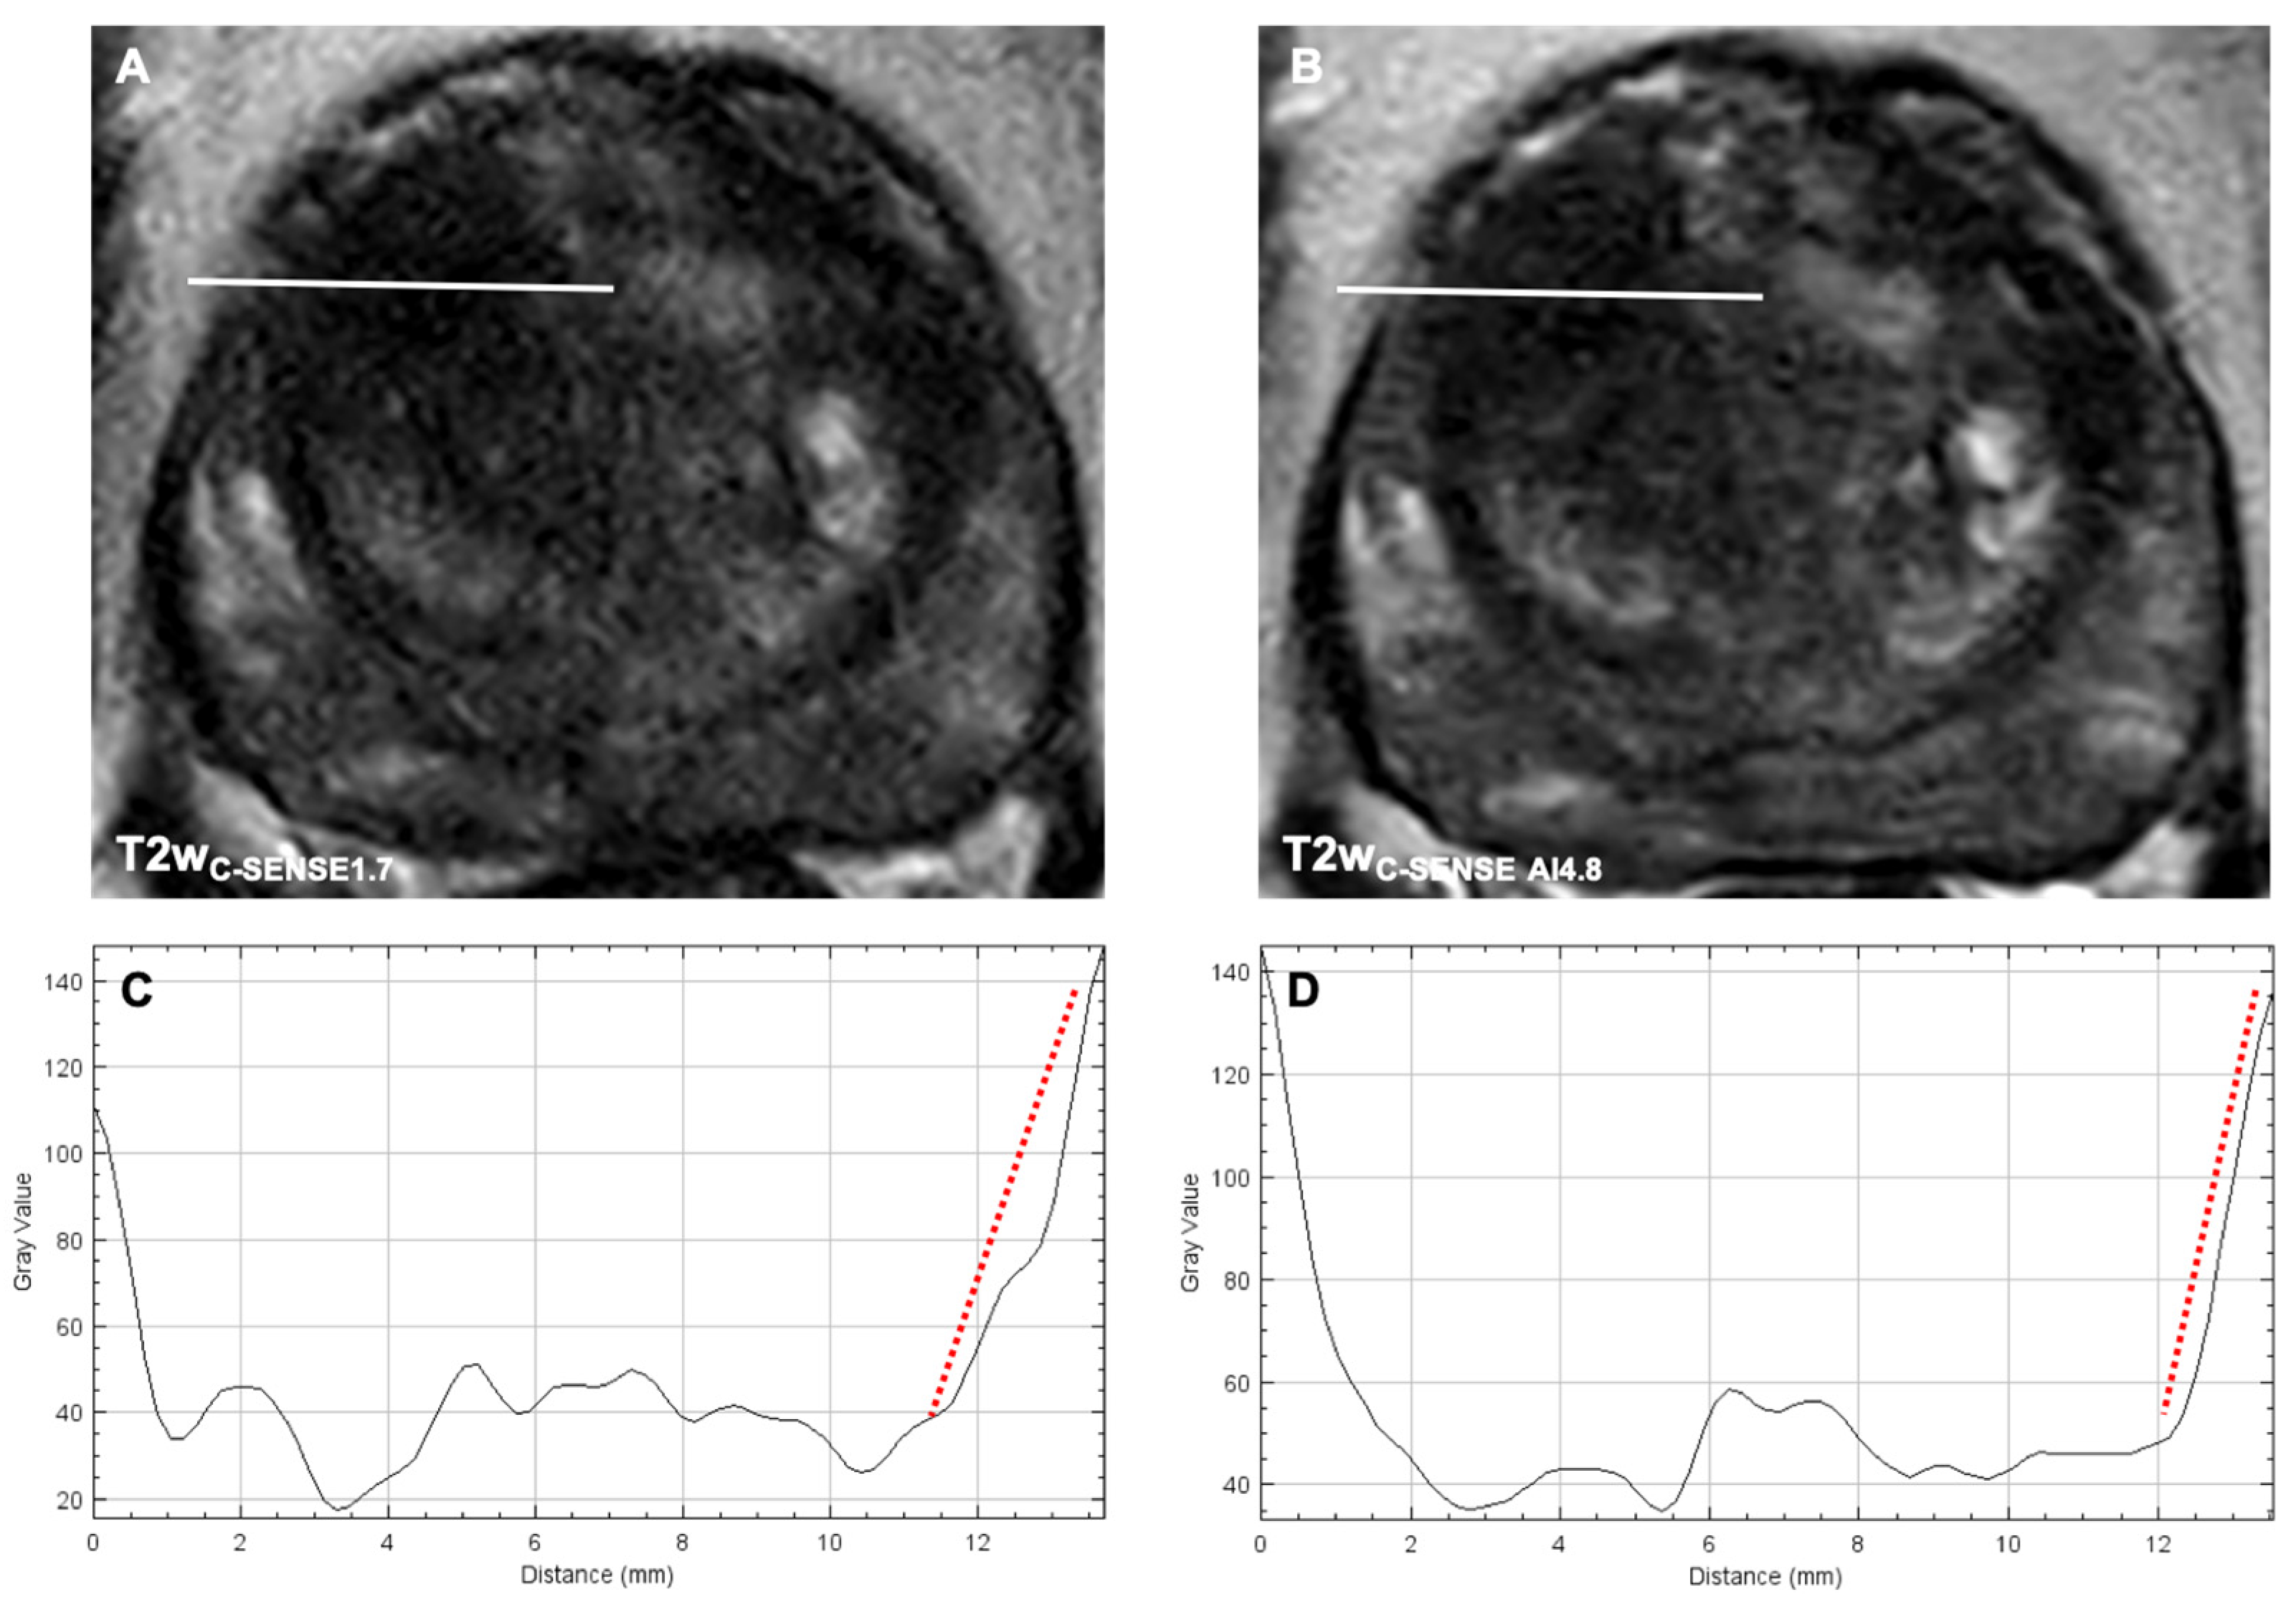

3.3.3. Image Sharpness

3.3.4. Lesion Size